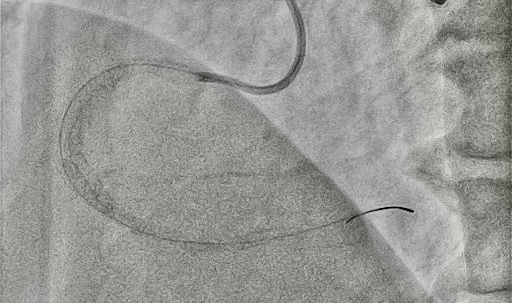

A Convey CLS 4 6F guiding catheter (Boston Scientific) was engaged in the left main coronary artery, and an Amplatz left 1 7F was engaged in the ostium of the RCA. Starting from the antegrade with a Gladius EX guidewire (Asahi) and a Turnpike Spiral microcatheter (Teleflex), a dissection reentry was attempted. Τhe Gladius EX, the Gaia Next 2 (Asahi), the Confianza Pro 12 (Asahi), and the Hornet 14 (Boston Scientific) were used consecutively, passing inside the outer layer of the vessel (adventitia), next to the old stent, and reentering in the distal part of the RCA. In order to reenter the true lumen before the bifurcation, a Stingray balloon (Boston Scientific) was used. A Gaia Next 3 was advanced inside the Stingray, successfully reentering the lumen. Afterwards, balloon inflation was performed throughout the vessel and, finally, 4 stents were deployed with a good angiographic result and Thrombolysis in Myocardial Infarction-III flow (Figures 1 and 2, Videos 1 and 2). The patient was discharged the next day.